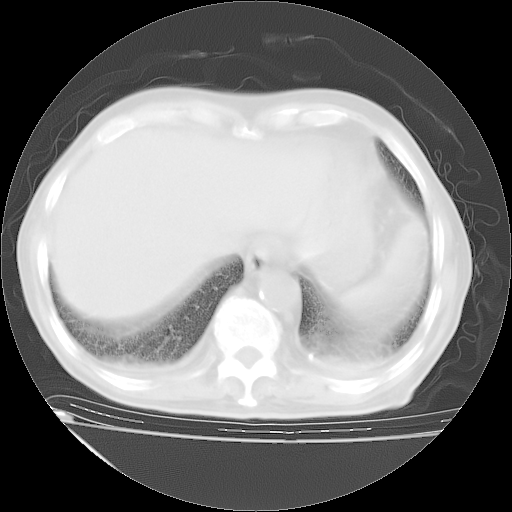

经过24天治疗,岳父的病情基本稳定。生活基本可以自理,可以下床活动。呼吸困难早已消失。体温基本正常。

只是甲强龙用80mg时血小板升到正常,改为60mg后又降到63×10*9/L。

主要治疗甲强龙80mg×14天,60mg×10天;同时抗结核(异烟肼+利福平+乙胺丁醇)。环磷酰胺0.1 tid 10天。

特别感谢胡教授、高管、桃子版主给出关键的治疗建议。桃版把所有肺部影像和全部临床资料请所在医院呼吸科、感染病科、结核科、临床免疫科专家会诊。临床免疫科专家制定了完整的治疗方案。